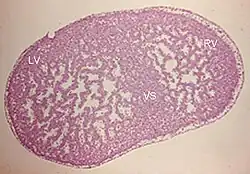

Niescalony mięsień lewej komory (ang. noncompaction cardiomyopathy, left ventricular non-compaction, LVNC) – heterogenna etiologicznie, uwarunkowana genetycznie nieprawidłowość rozwojowa mięśnia lewej komory serca, zaliczana obecnie według klasyfikacji ESC do kardiomiopatii niesklasyfikowanych, a wedle klasyfikacji AHA do kardiomiopatii pierwotnych genetycznych[2], charakteryzująca się wzmożonym beleczkowaniem lewej komory i pogłębieniem zatok międzybeleczkowych. Istnieją rozbieżne opinie co do charakteru LVNC; część badaczy jest zdania, że stanowi odrębną kardiomiopatię, podczas gdy inni widzą w niej cechę wspólną wielu fenotypowo odmiennych postaci kardiomiopatii.